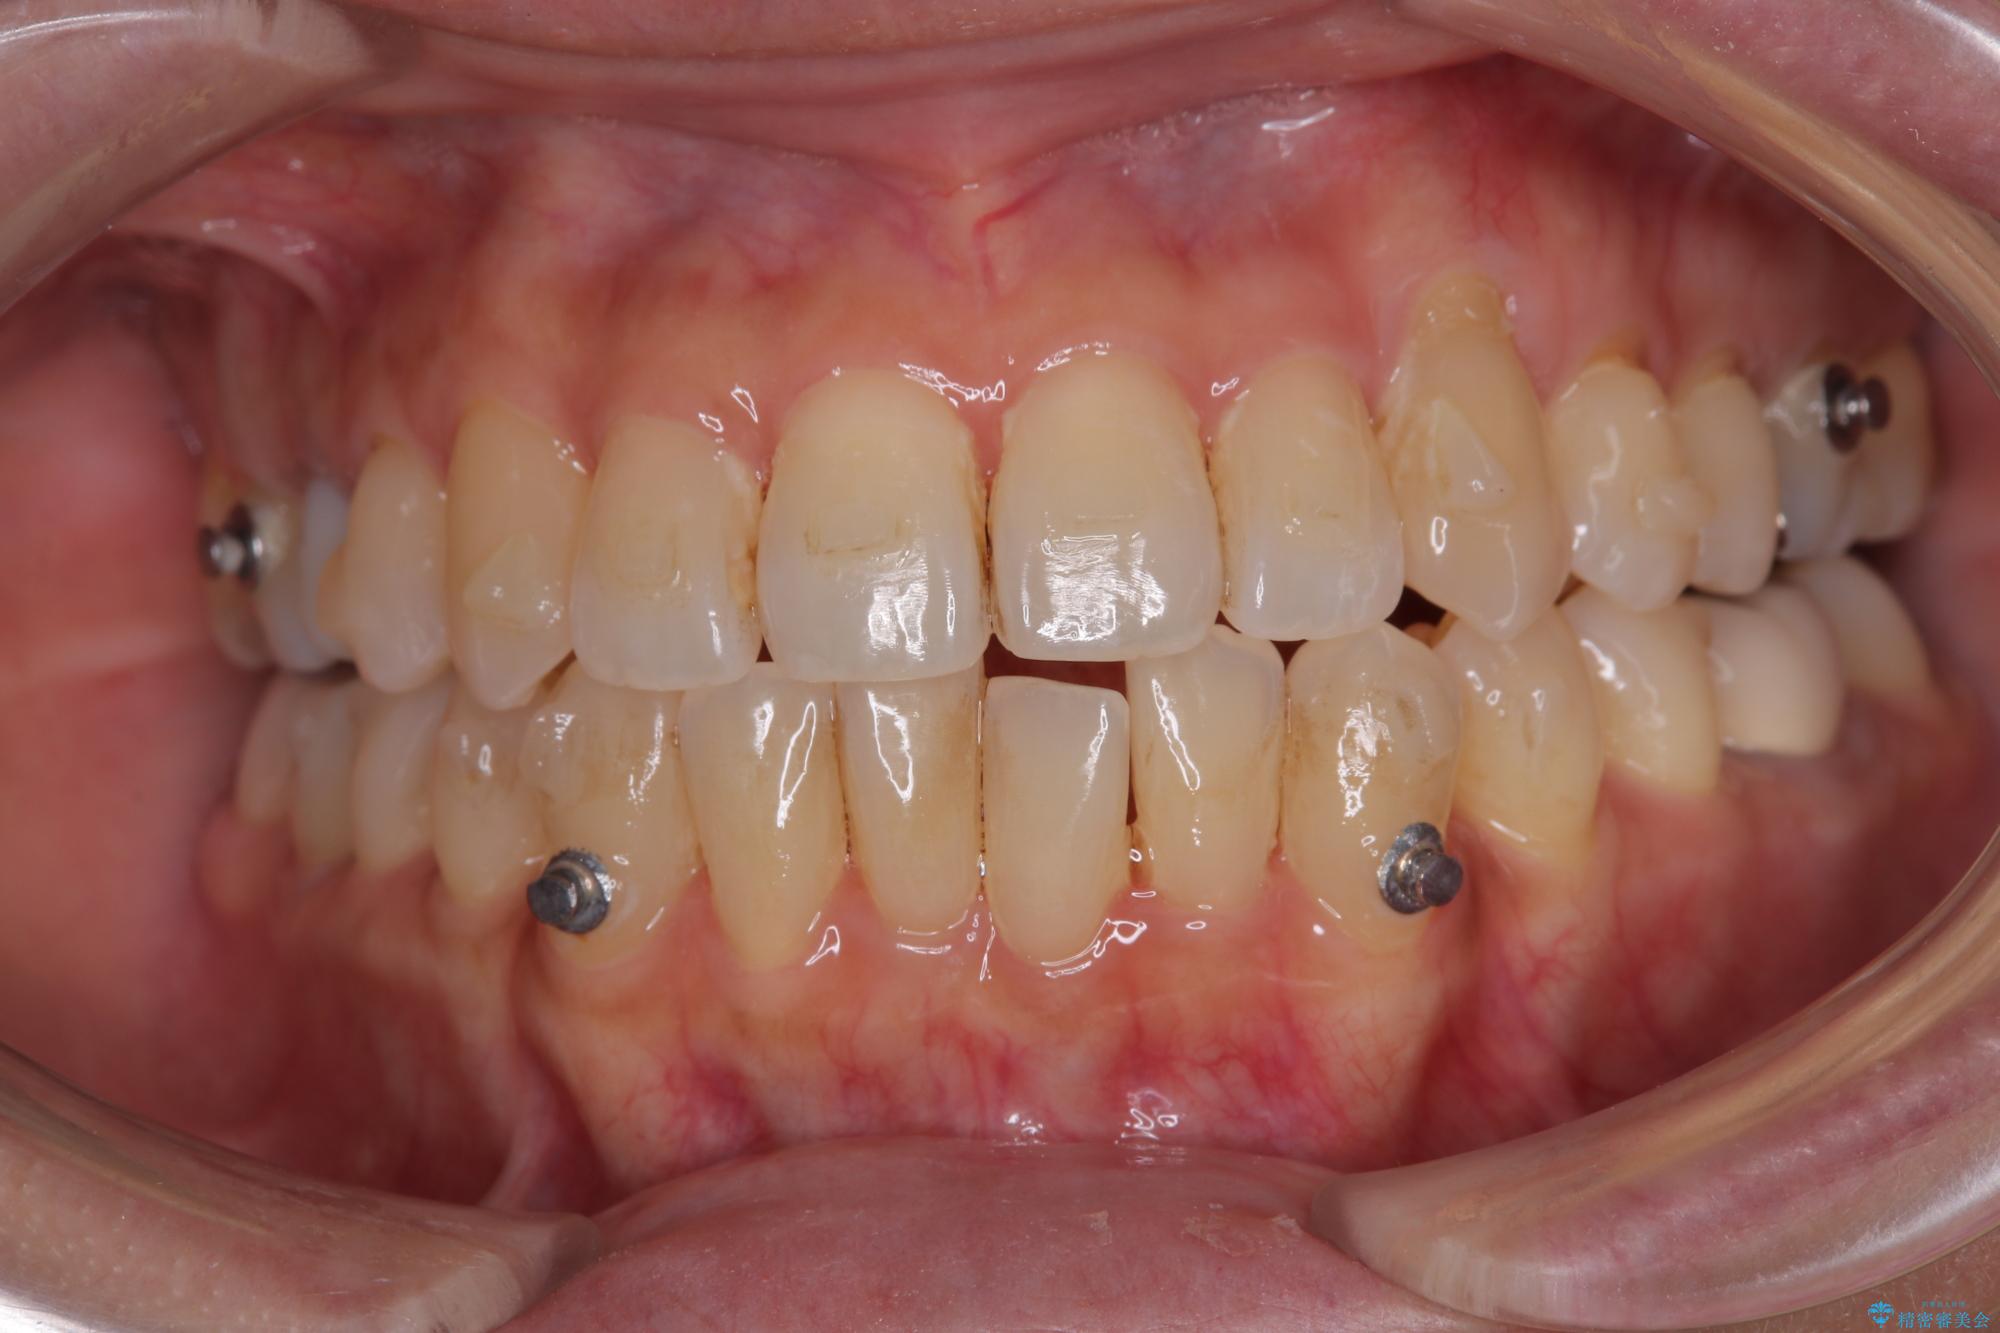

- 前歯のデコボコや八重歯を治したいとのことで来院された患者様です。

受け口傾向の骨格であり、前歯はクロスバイトまたは切端咬合となっており、下顎を中心に歯列全体の後方移動を行い、IPR(歯と歯の間を削る)によってデコボコが解消するように設計し、インビザラインにより治療を行うこととしました。

受け口傾向のインビザライン矯正は比較的治療を行いやすいため、きれいに仕上げることができました。舌の突出癖が顕著であったため、改善のためのトレーニングをしっかりと行っていただきました。